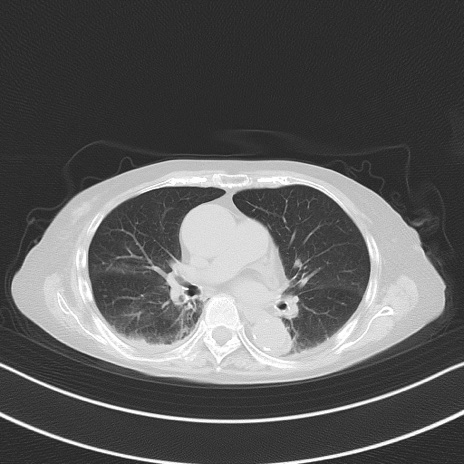

横断像

他院CT